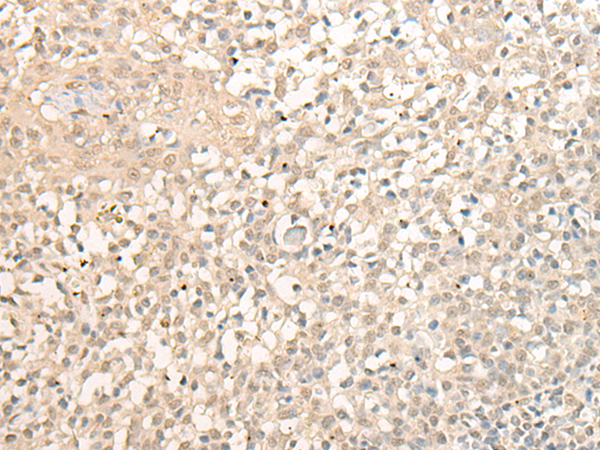

分类: 科研抗体货号: P09616别名: DEM1; Exo V; hExo5; C1orf176应用: IHC反应种属: Human, Mouse